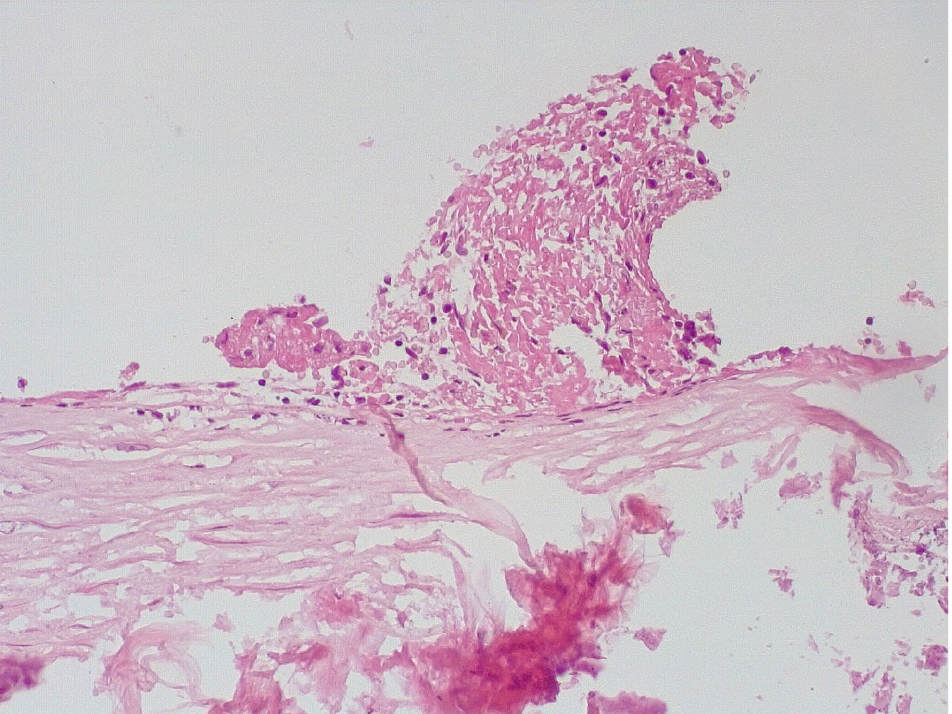

Патоморфологическое исследование стенок КА в ранние сроки после стентирования выявило характерные особенности. В течение первых 3 дней после стентирования в стенке КА имелась атерома с признаками геморрагий. Эндотелий был на большем протяжении разрушен, с признаками десквамации, с окружающей очаговой лейкоцитарной инфильтрацией. Вокруг атеромы, со стороны медии и адвентициальной оболочки, отмечалась умеренновыраженная лимфоцитарная инфильтрация (рис. 1).

Позднее, спустя 3–7 суток после стентирования КА в просветах имелись пристеночные смешанные фибриново-лейкоцитарные тромбы, которые могли служить источником развития тромбоэмболических осложнений мелких дистальных ветвей коронарного кровотока и развитием острого инфаркта миокарда (рис. 4).

Проведенное морфоиммуногистохимическое исследование КА после стентирования в ранние сроки показало определенные закономерности их поражения. Было показано, что в течение первых 3 дней после стентирования КА в их стенках наблюдаются острые повреждения клеток эндотелия в виде десквамации, дистрофических и некробиотических процессов, внутристеночные геморрагии в зонах локализации атером.